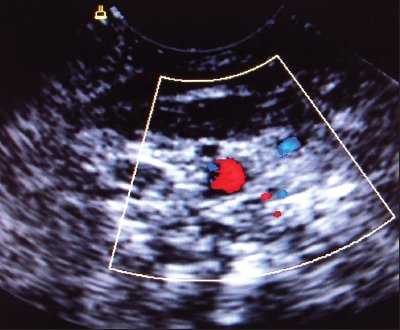

Одной из проблем при катетеризации центральных вен является корректная позиция центрального венозного катетера, при которой его конец должен находиться в полости верхней полой вены над правым предсердием. По данным отечественных и зарубежных исследователей, некорректная позиция центрального венозного катетера против тока крови встречается в 0,5-18% случаев (в 5-18% при катетеризации v. subclavia и в 0,5-5% при катетеризации v. jugularis interna). Наиболее частым вариантом некорректной позиции является расположение катетера в полости внутренней яремной вены при катетеризации одноименной подключичной вены (рис. 6). В настоящее время существует несколько методов верификации позиции центрального венозного катетера: рентгено-контроль, ЭКГ-контроль; одним из них на практике становится УЗИ для уточнения положения центрального венозного катетера (рис. 7, 8).

Рис. 7. Тот же катетер в просвете внутренней яремной вены при поперечном сканировании.